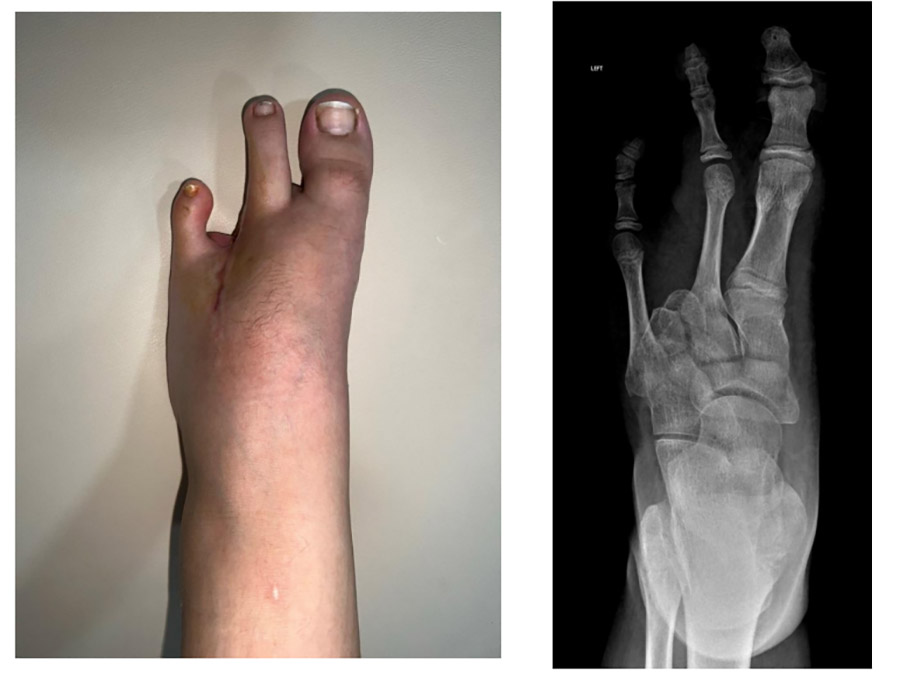

Ameliyat Sonrası: Ray amputasyon sonrası yara iyileşmesi ve röntgen görüntüsü görülmekte